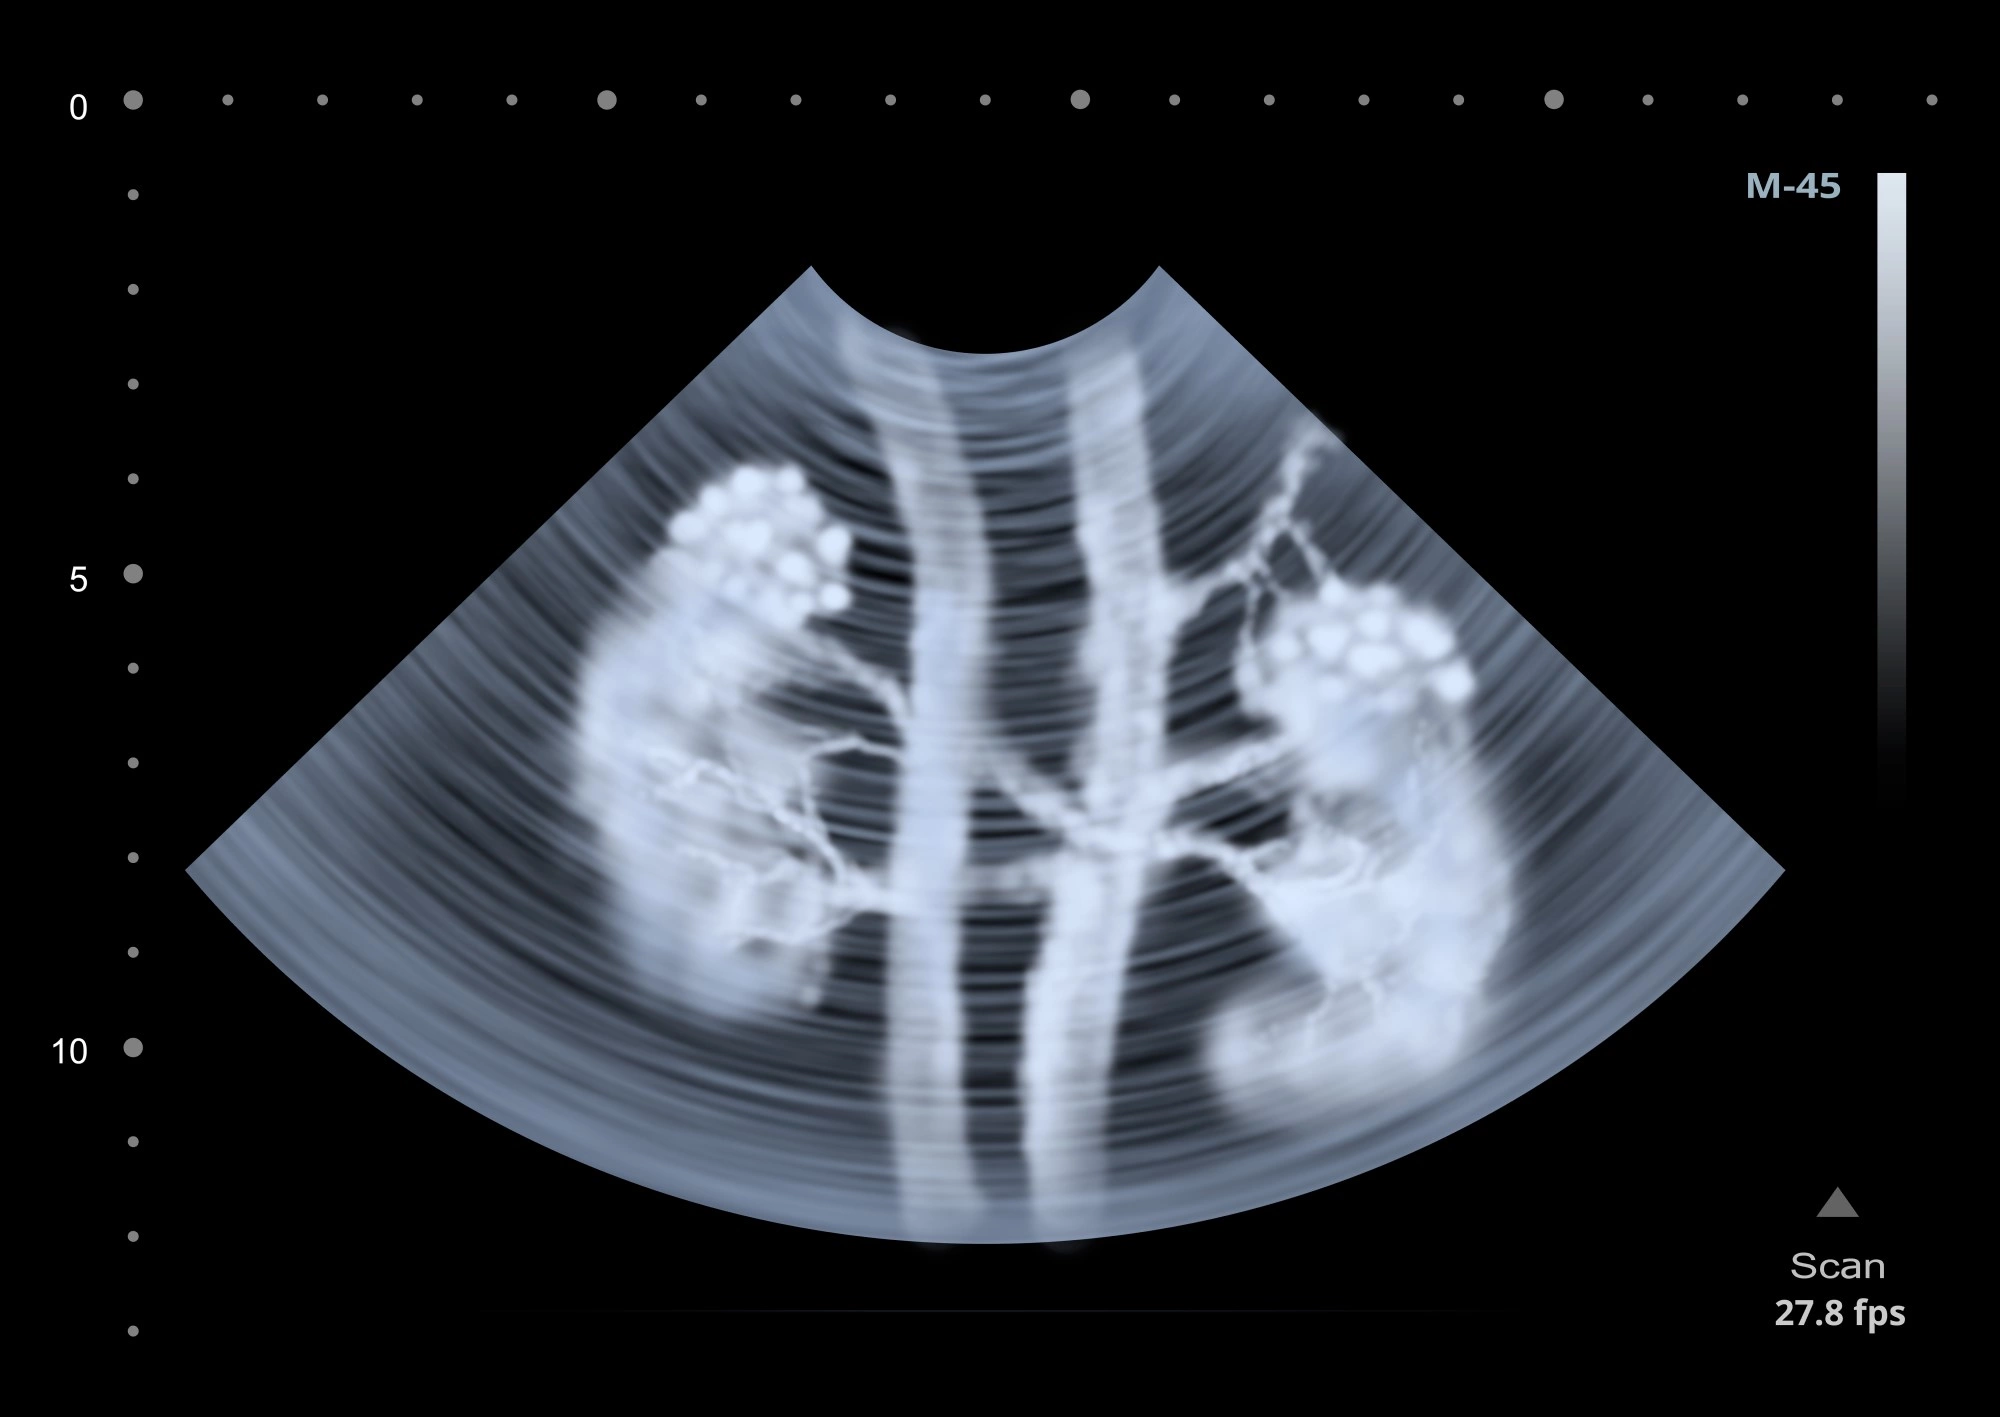

УЗИ почек

Что такое УЗИ почек

Ультразвуковое исследование почек — это малоинвазивная диагностическая процедура, которая дает возможность определить форму, размер и локализацию органа, а также наличие новообразований. С помощью этого обследования врач визуализирует структуру тканей и почечный кровоток. Часто одновременно с почками проводится и исследование мочевого пузыря.

УЗИ почек является доступной и безопасной процедурой. Принцип его работы основан на эхолокации: датчик, контактирующий с кожей, одновременно выполняет роль излучателя и приемника ультразвука. Ультразвуковые лучи проникают через кожу и отражаются в разной степени от плотных органов. Отраженный ультразвук регистрируется датчиком и преобразуется в изображение, которое транслируется на экран оборудования. Исследование не предполагает использование рентгенологических лучей, поэтому пациент не подвергается даже минимальной лучевой нагрузке. Благодаря этому обследование проводится даже детям и беременным женщинам.